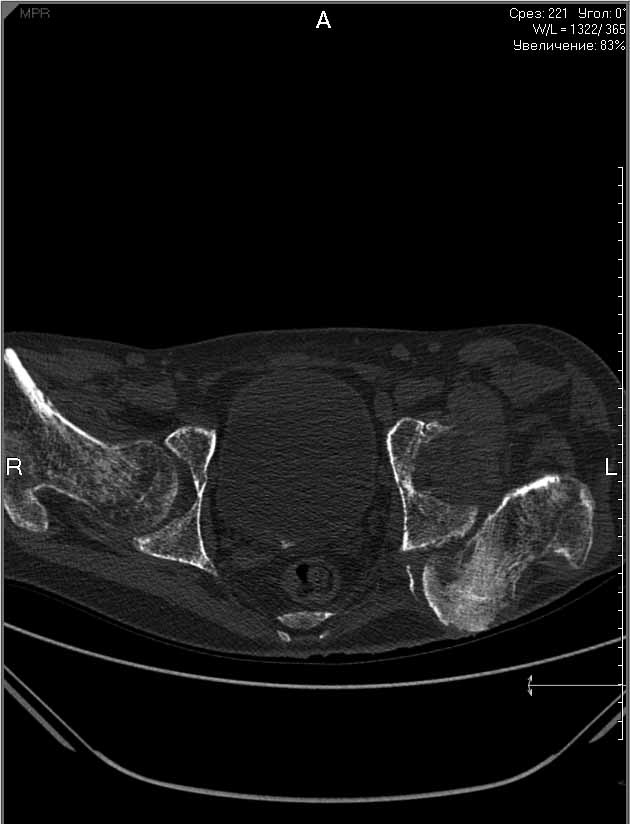

Пациенту 22 года. Травма в июле 2010г, лечился в районной больнице. К нам попал в апреле 2011г.Тяжелая сочетанная травма (29.07.2010): тупая травма живота с повреждением внутренних органов. Закрытая травма грудной клетки с переломом ребер. Пневмоторакс справа. Тяжёлая позвоночно-спинномозговая травма. Закрытый осложнённый переломо-вывих С5 позвонка. Верхний парапарез, нижняя параплегия, нарушение функции тазовых органов по типу недержания. Цекостома. Пролежень левой ягодичной области. Неправильно консолидированные переломы верхних третей обеих бедер. Застарелый вывих левого бедра.Осложнение: Поддиафрагамльный абсесс слева, забрюшинного пространства. Свищ желудка и ободочной кишки. Синегнойный сепсис. Двухстороняя пневмония. Но это уже анамнез.Пациент был неоднократно оперирован на органах брюшной полости и осложнениями с ними связанными.

В ягодичной области слева глубокий пролежень размером 2х2см, дном является вывихнутая головка бедра. Неврологически в нижних конечностях динамика положительная, появились движения в правой стопе, чувствительность в стопах.По переломам бедер: подвижности в местах переломов нет, снимки высылаю.

Планирую начать с правого бедра, ЧКО таза (передняя рама) с фиксацией бедра. О/клазия места перелома правого бедра и устранение грубых смещений в аппарате. окончательно можно оставить и в аппарате. Далее аппаратное устранение вывиха левого бедра.